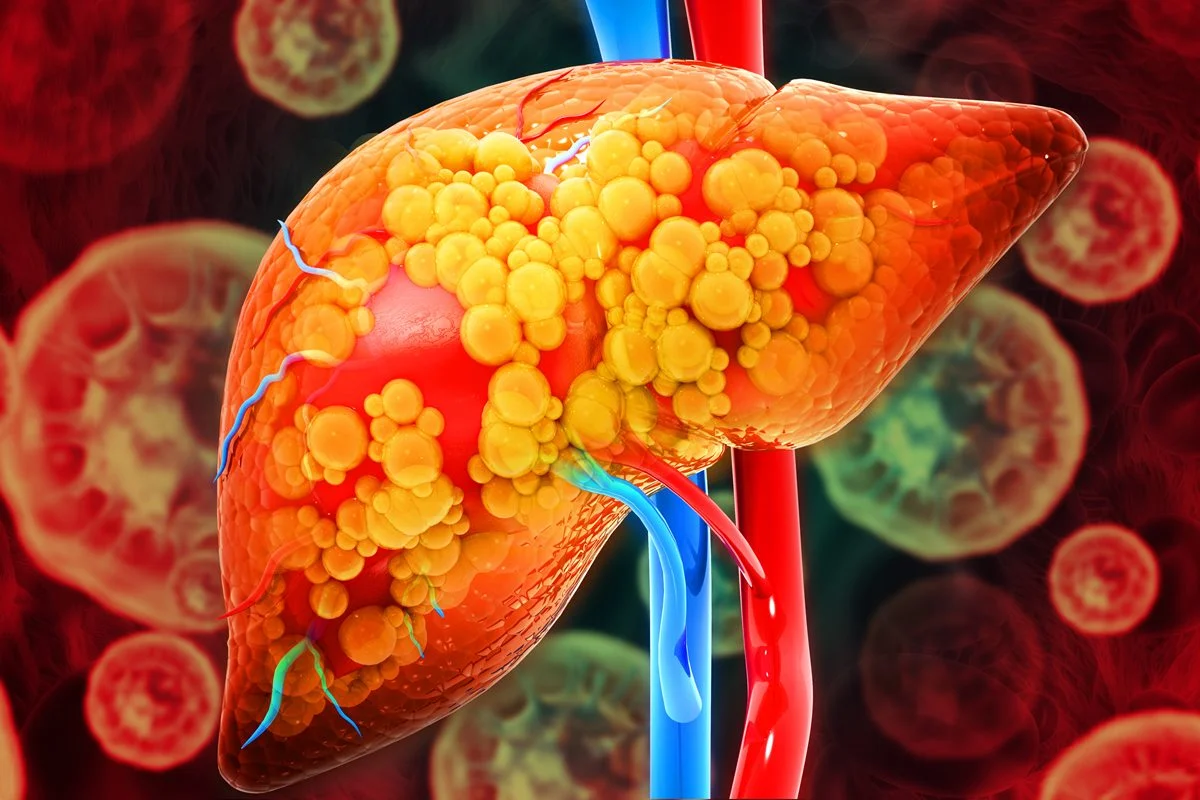

Science Photo Library – SCIEPRO/Getty Images

A esteatose hepática ocorre quando há um acúmulo excessivo de gordura (triglicerídeos) nas células do fígado, ultrapassando cerca de 5% do peso total do órgão. Esse acúmulo pode ser resultado de vários fatores, e o mais comum é o desequilíbrio metabólico do organismo.

- Popularmente chamada de gordura no fígado, a esteatose hepática acontece quando as células do órgão acumulam gordura em excesso.

- As principais causas estão relacionadas à obesidade, ao diabetes, ao colesterol alto e ao consumo excessivo de álcool.